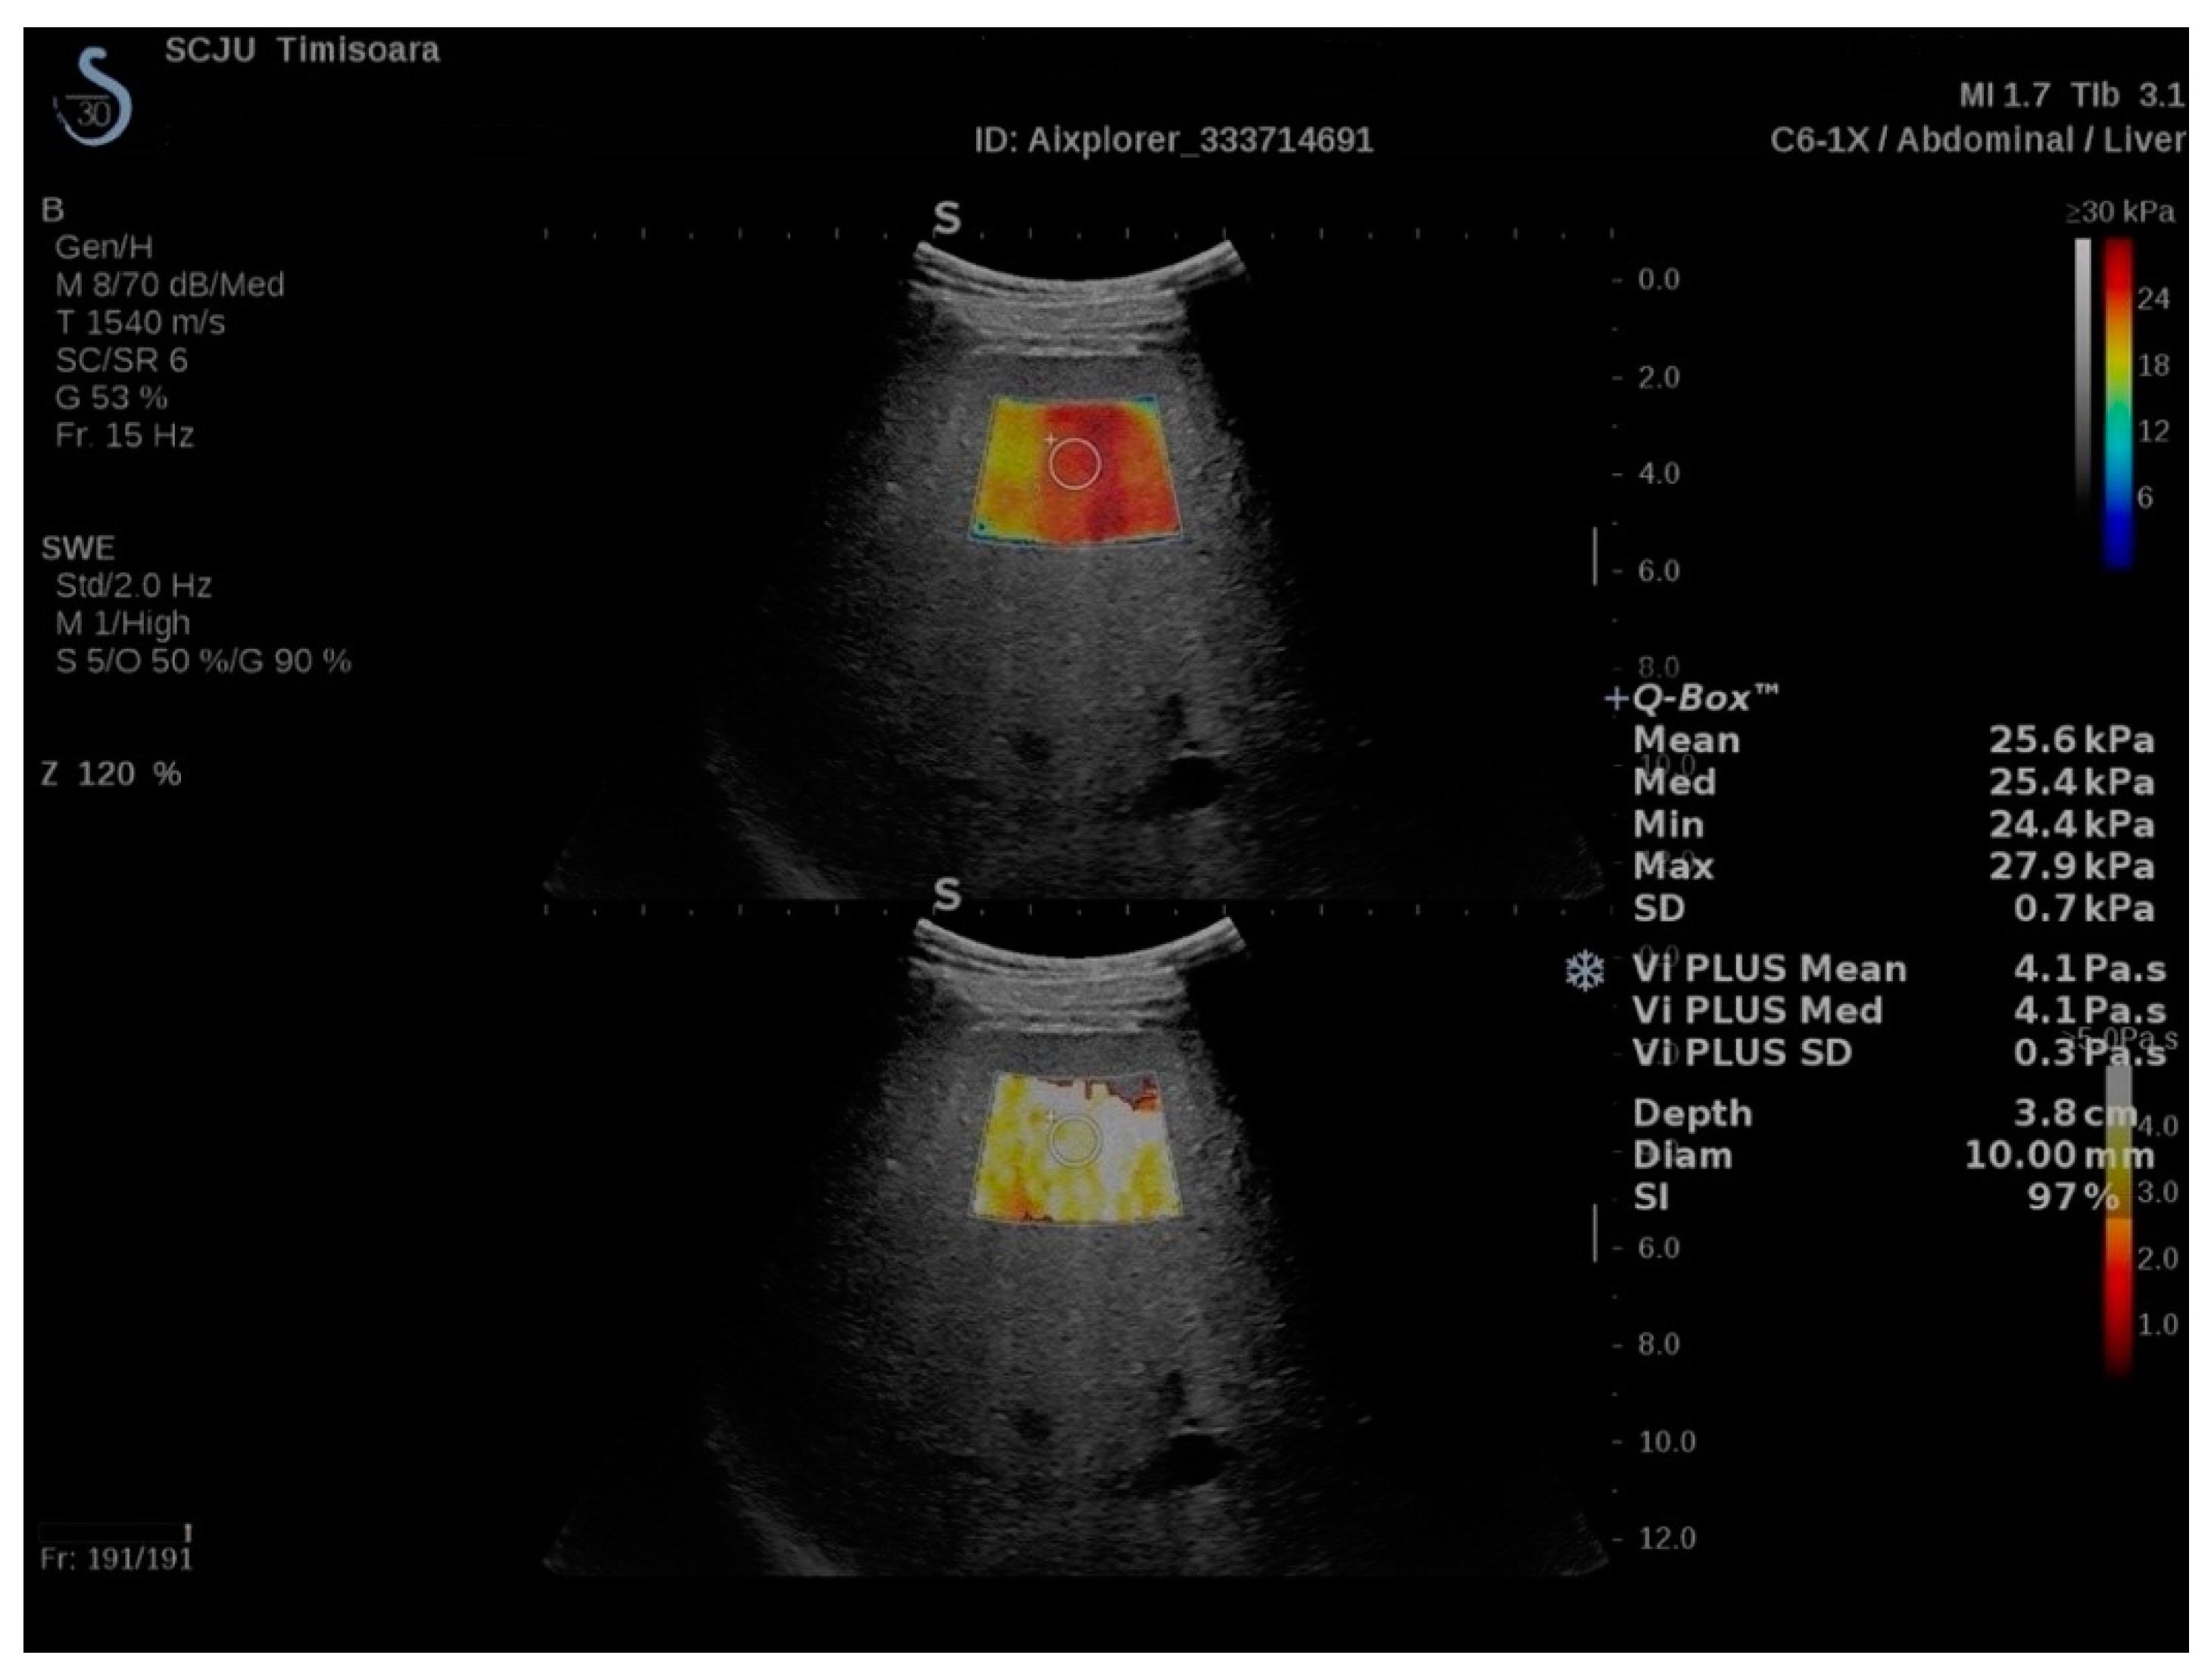

2.2. ShearWave PLUS Elastography

2.3. Viscosity PLUS

2.4. Attenuation PLUS and Sound Speed PLUS Break to Next Page